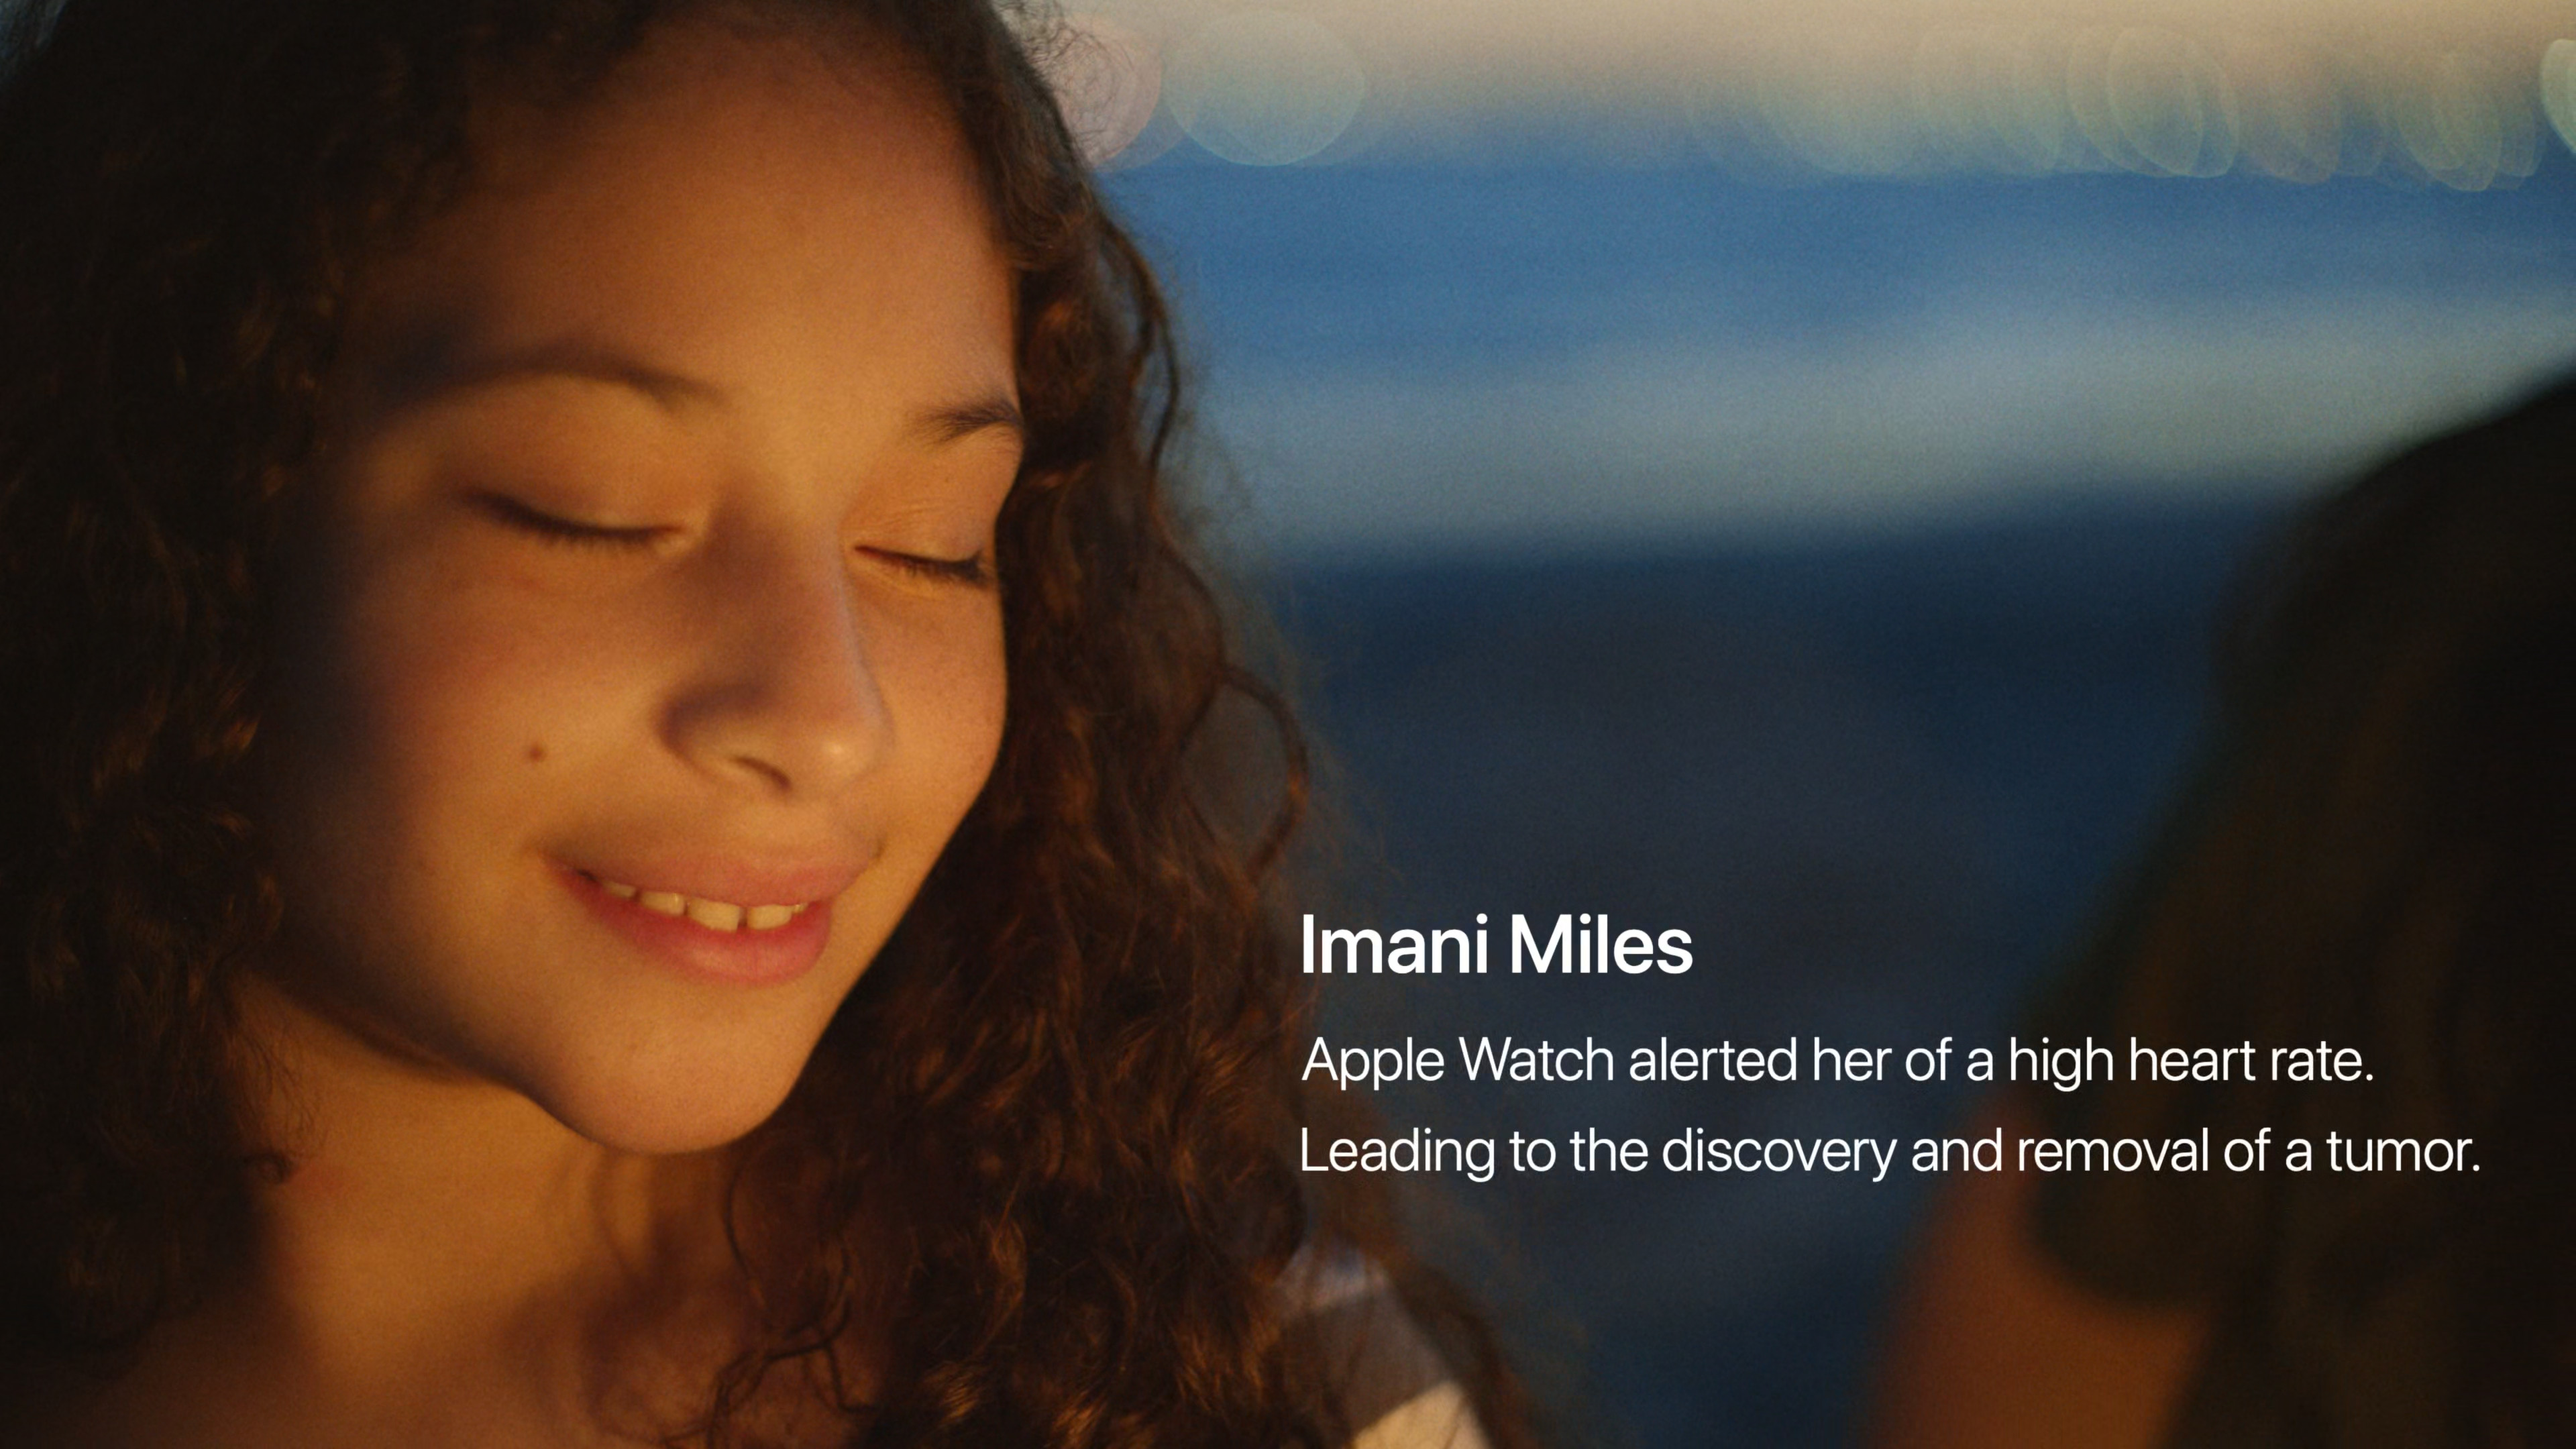

Již několik desítek minut před začátkem se na webu Applu objevilo logo letošní Keynote za doprovodu skladby Natural od Jackie Mendozy a Magic in U od Cub Sport. Jakmile odbila sedmá, animace se změnila v tradiční úvodní video se záběry na různé lidi, jak v průběhu dne od probuzení až do noci používají nejrůznější Apple zařízení. Po přehrání emotivního videa, zmiňujícího mimo jiné přínos Apple Watch a dalších jablečných produktů a jejich funkcí pro lidské zdraví, jsme se mohli pokochat klasickým přeletem nad Apple Parkem. V němž nás již přivítal Tim Cook a zahájil nejdůležitější Apple Keynote letošního roku, na které se představí iPhone 15, iPhone 15 Pro (Max), Apple Watch Series 9 a spousta dalších novinek.